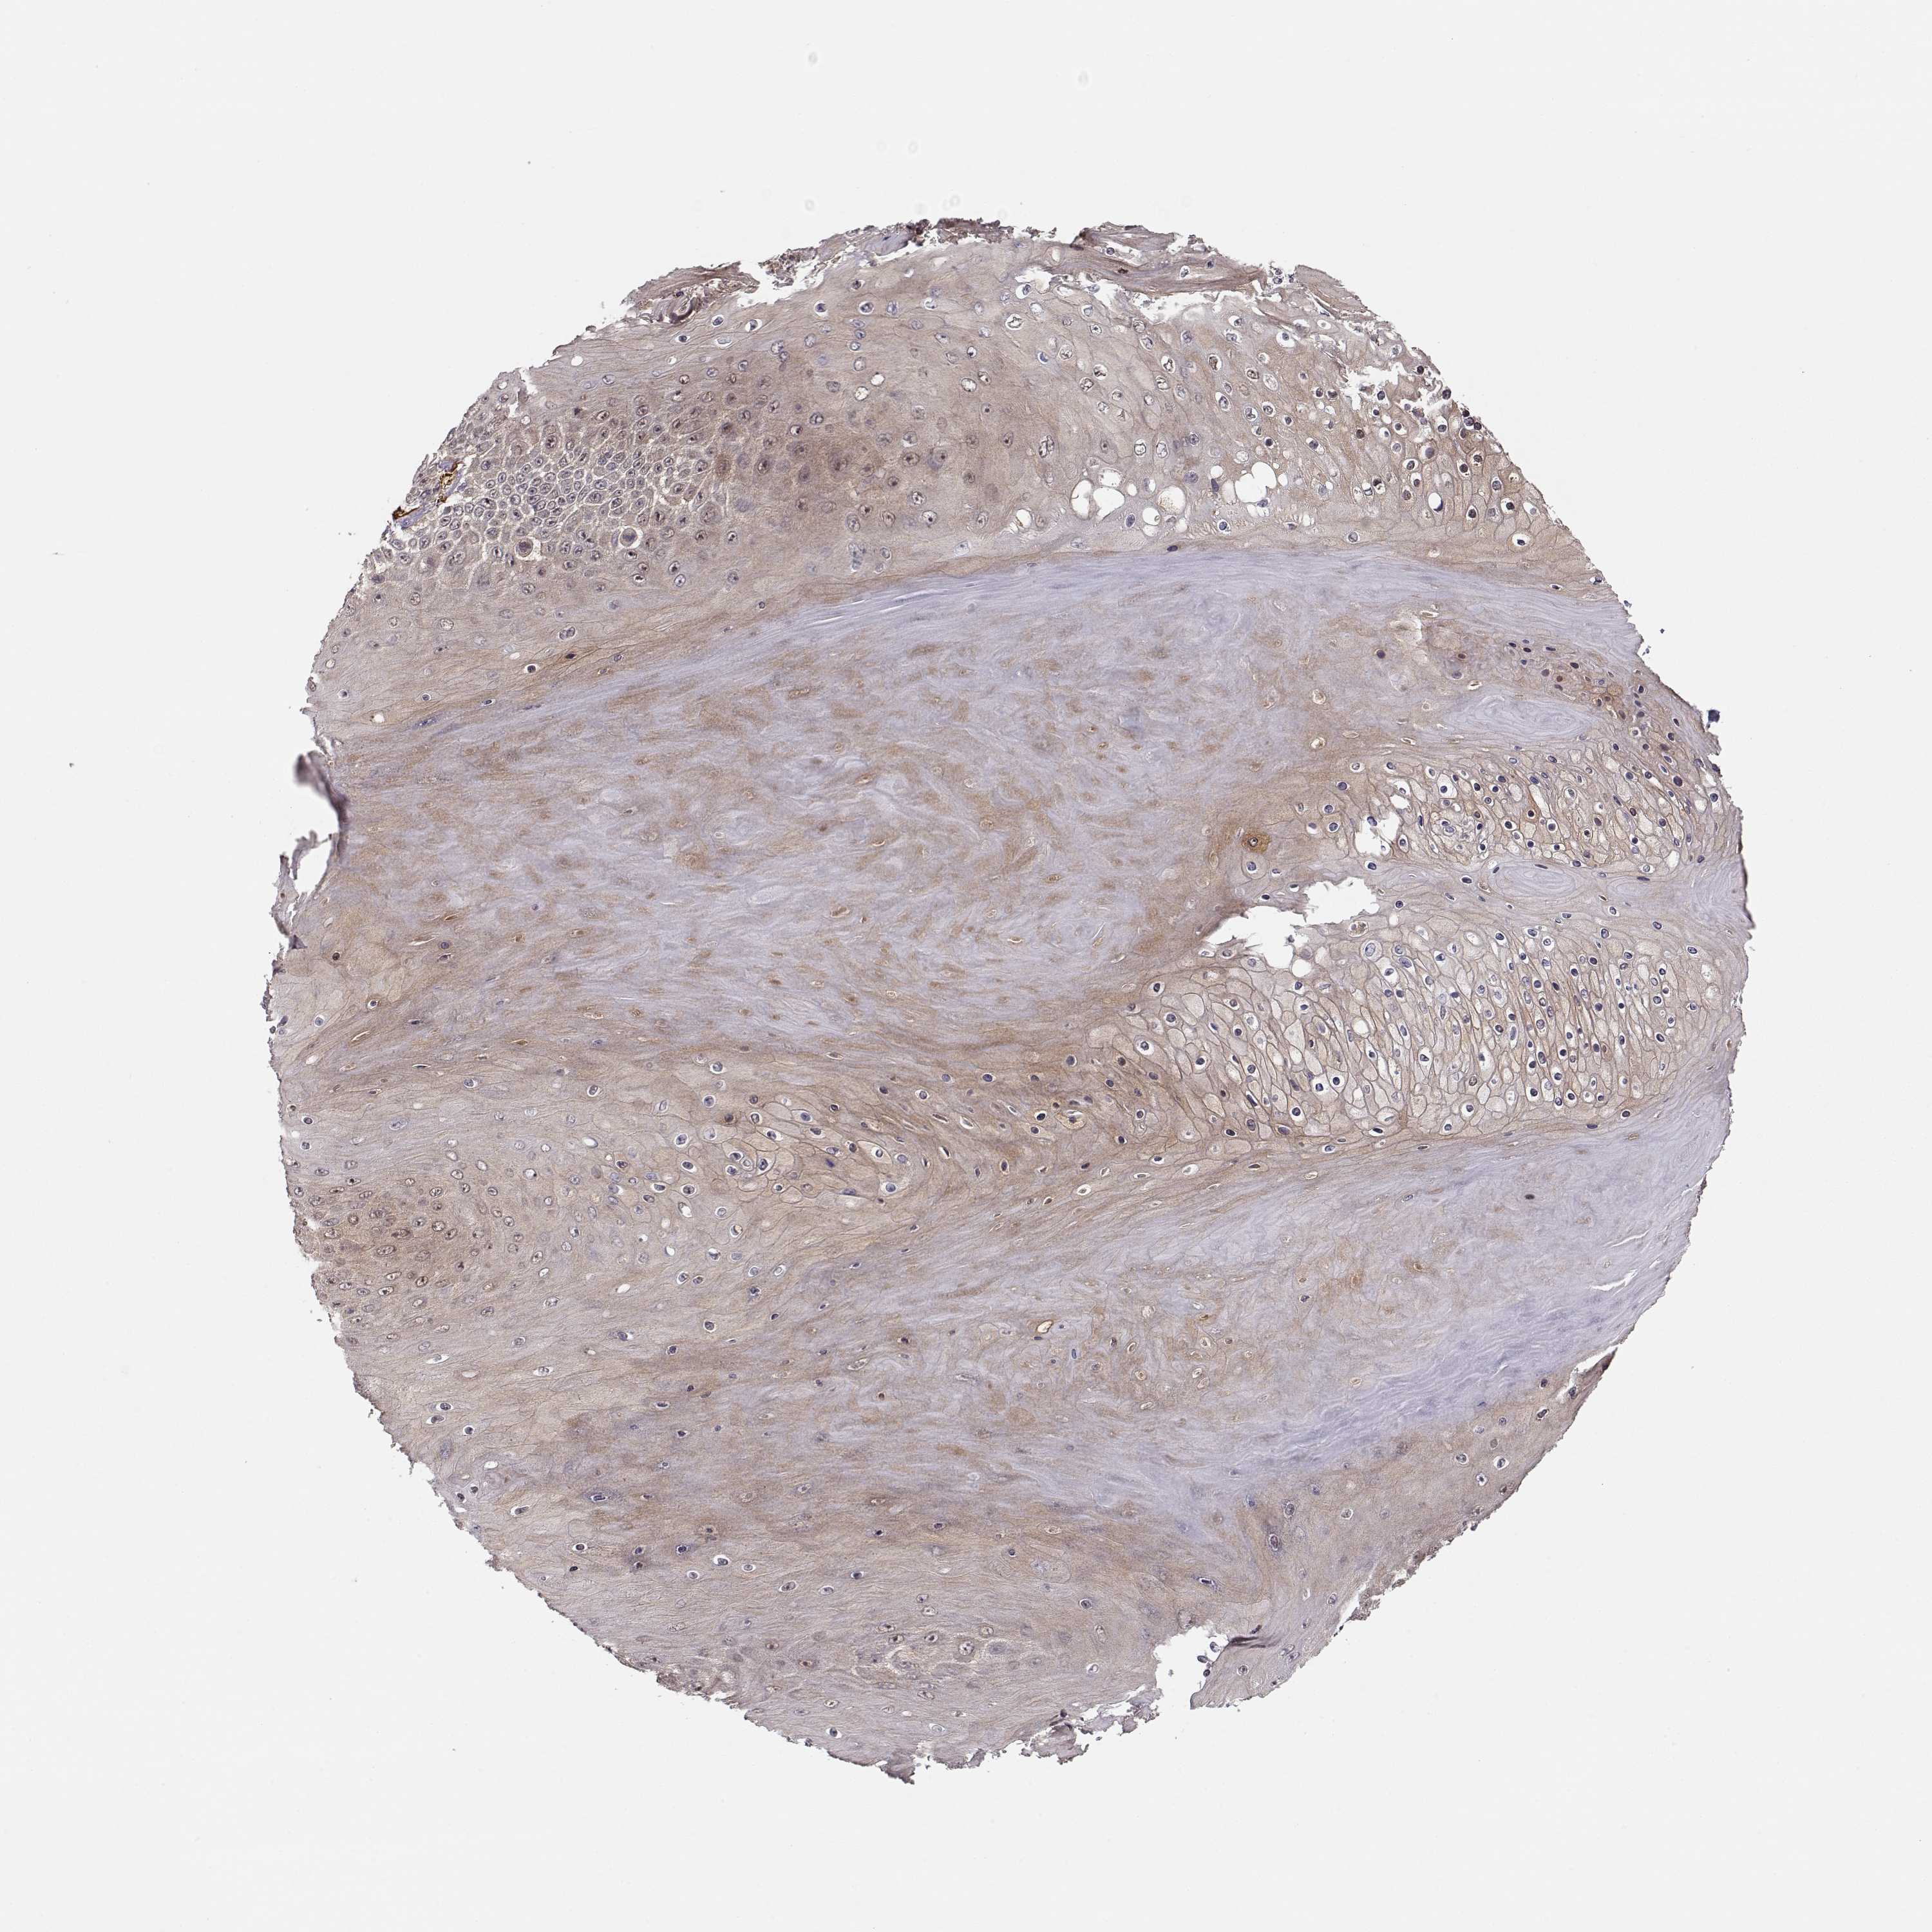

SKIN CANCER - Protein expressioni

A mouse-over function shows sample information and annotation data. Click on an image to view it in a full screen mode. Samples can be filtered based on level of antibody staining by selecting one or several of the following categories: high, medium, low and not detected. The assay and annotation is described here.

Antibody stainingi

Antibody staining in the annotated cell types in the current human tissue is reported as not detected, low, medium, or high, based on conventional immunohistochemistry profiling in selected tissues. This score is based on the combination of the staining intensity and fraction of stained cells.

Each image is clickable and will lead to virtual microscopy that enables deeper exploration of all samples and also displays staining intensity scores, fraction scores and subcellular localization as well as patient and tissue information for each sample.

Antibody HPA001625

Staining

High

Medium

Low

Not detected

Intensity

Strong

Moderate

Weak

Negative

Quantity

>75%

75%-25%

<25%

None

Location

Nuclear

Cytoplasmic/membranous

Cytoplasmic/membranous,nuclear

Squamous cell carcinoma, NOS

Basal cell carcinoma